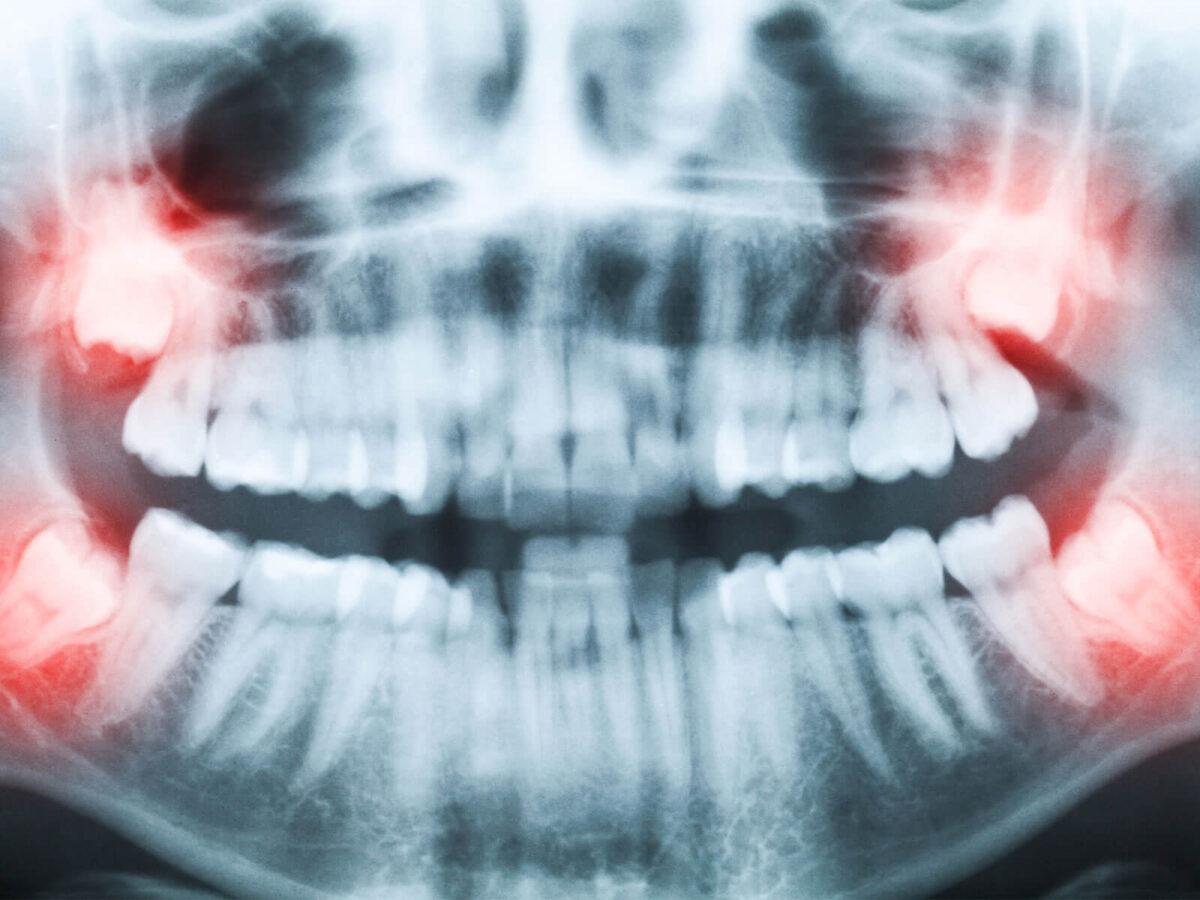

From the outside, a mouth can look fine. Teeth look clean. Gums don’t hurt. Nothing feels wrong. But inside the mouth, things can be very different. Cavities can grow between teeth. Bone levels can slowly change. Infections can sit quietly without causing pain.

Bitewing X-rays are used a lot to look for cavities between teeth. Those areas are easy to miss just by looking. Teeth can look clean. Nothing obvious shows up during the exam. That doesn’t always mean nothing’s going on.

Cavities between teeth are easy to miss just by looking. Because of that, bitewings end up being taken more often than most other X-rays. The timing depends on cavity risk. For some, that may mean once a year. For others, it could be longer. This is where people often notice differences between visits and wonder why timing isn’t consistent.

X-rays aren’t only about cavities. They also show bone levels around teeth. Bone loss happens slowly, and early changes don’t cause pain.